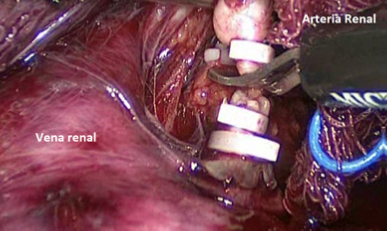

Una manera segura y sencilla de acceder al hilio renal es disecar la Gerota en su extremo caudal, separándola de su íntima unión con el músculo psoas lumbar. Una vez ubicado el hilio, este debe ser disecado para controlar por separado arteria y vena. Usamos Hem-o-LockTM de rutina, dos proximales y uno distal (Figura 21).

Inicialmente, se accede por vía transperitoneal al riñón derecho, movilizando el colon y realizando una maniobra de kocher amplia para llegar sin dificultad al hilio renal y a los grandes vasos. Se debe disecar al vena cava por encima y por debajo del hilio renal, especialmente en su cara posterior. De manera habitual, se controlan y seccionan las arterias renales.

Posteriormente, con pinzas atraumáticas se evalúa la posición del trombo en la cava. Se introduce una pinza Satinsky laparoscópica y se pinza parcialmente la vena cava, incluyendo el trombo. Esta maniobra evita el sangrado retrógrado por las venas lumbares que se produce al pinzar la cava en sus puntos distal y proximal a la afluencia de la vena renal. Se liga y secciona la vena renal, para tener mayor maniobrabilidad en el manejo de la vena cava. Se completa la disección de la pieza quirúrgica para tener mayor comodidad en la trombectomía. Luego, se efectúa la cavotomía con tijera fría y se extrae trombo. Finalmente, se sutura vena cava con polipropileno 4/0 y se comprueba hermeticidad (Figura 23).

Quienes hemos tenido la experiencia de operar tumores renales con trombos en la cava, hemos sufrido el sangrado que se produce al no tener controladas las venas lumbares. Con trombos hasta nivel II (clasificación de Novick)(25) es posible realizar este procedimiento en forma segura cuando se cuenta con pinzas Satinsky laparoscópicas, disponibles en el mercado. Cuando no se cuenta con estos elementos o el trombo sobrepasa este nivel, es preferible hacer una cirugía abierta.